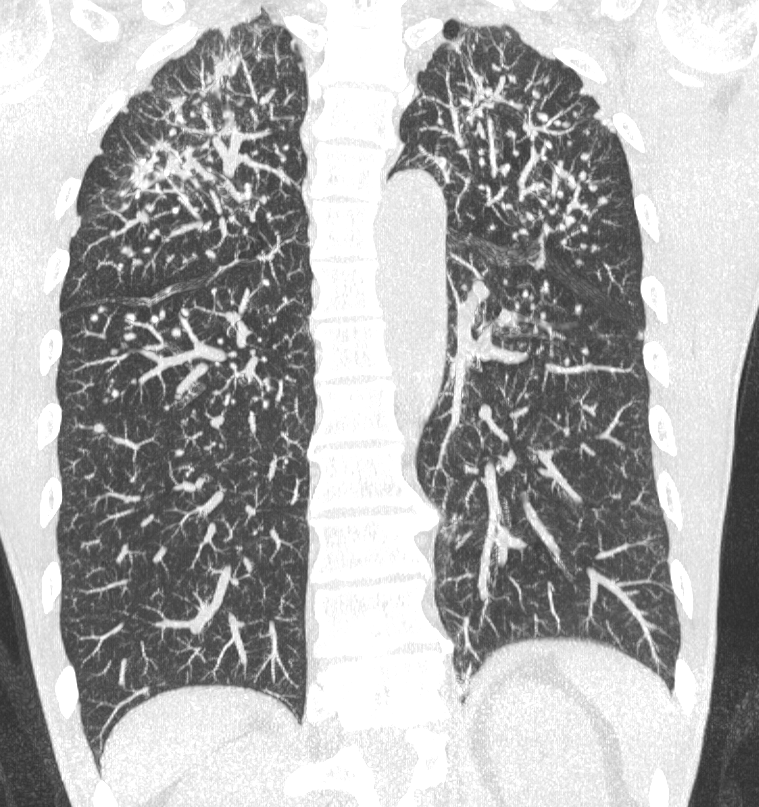

肺部高分辨率计算机断层扫描(HRCT)显示多个边界清晰的肺结节

,肺尖和周围易受累,肺底相对正常(图1和2)。结节的直径从约几毫米到一厘米不等,并显示散在钙化(图3)。在上叶这些结节显示出融合趋势;没有空洞形成。也有轻度肺气肿

以及弥漫性支气管壁增厚。患者最终诊断为Caplan综合征。

图1 冠状CT多平面重建显示许多边界清晰的肺结节,好发于肺尖和周围,大小从几毫米到1厘米不等